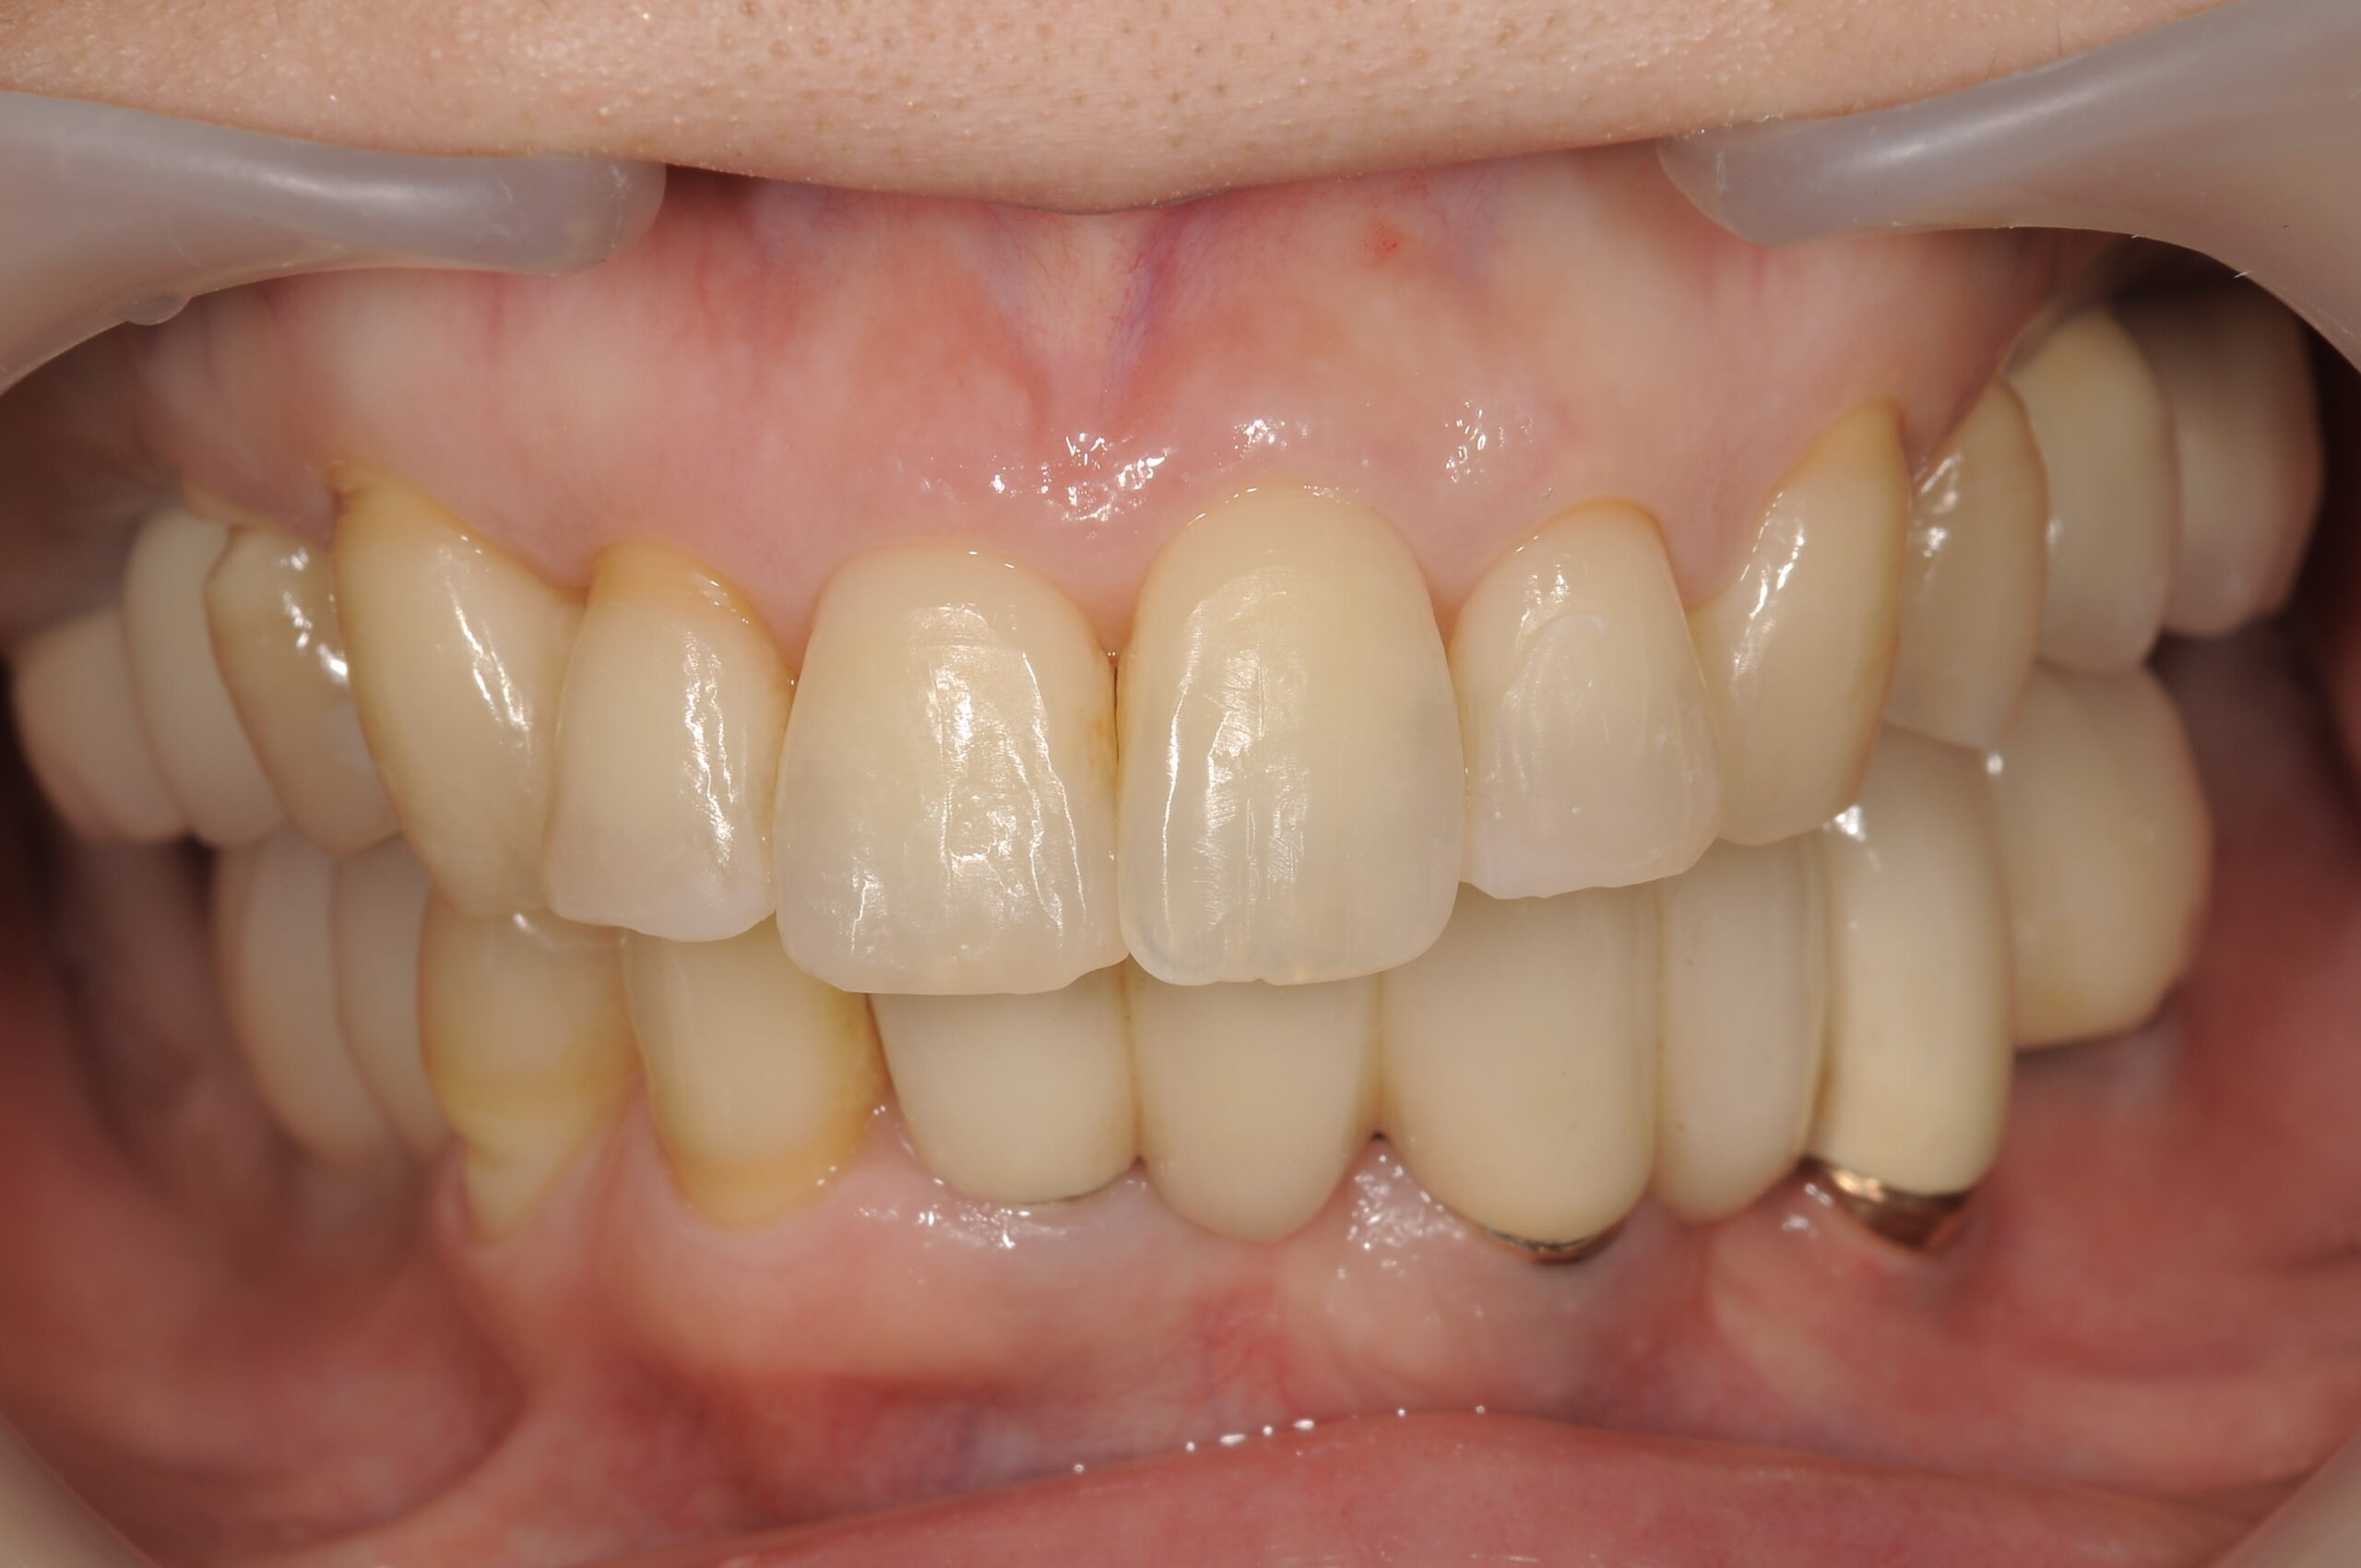

治療後の状態です。あごの調子もよくなりなんでもおいしく食べられるようになられました。

そして、ご自分の歯にはホワイトニングを行なってから、セラミックスの歯で審美的に治療を完了しました!

歯列不正もかなりありましたので、歯列矯正もおこないながら補綴的に咬合平面を整え、上顎にはサイナスリフト併用のインプラントを行い最終的には固定性の補綴物で機能回復を行いました。